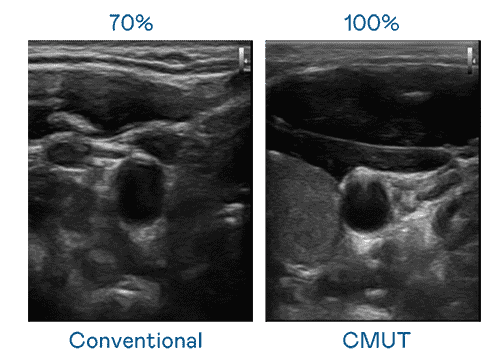

CMUT 技术是一种用电容式微机电元件来产生超音波讯号的技术。。与传统 PZT 压电式技术相比,,,CMUT 频宽增加 30%,,,更宽频的超音波讯号让影像解析度大幅提升,,,,是实现高影像品质医疗超音波扫描、、促进精准医疗发展的关键技术。。

大频宽带来超清晰影像

超音波影像的解析度高低,,首先取决于探头能发出的讯号频宽。。。。PA直营 CMUT 可提供高清晰的超音波讯号,,提供高频宽、、、、高灵敏度、、、影像纹理细节更高的超音波影像,,,,协助医护人员缩短影像判读时间及利用精准的医疗影像进行诊断。。